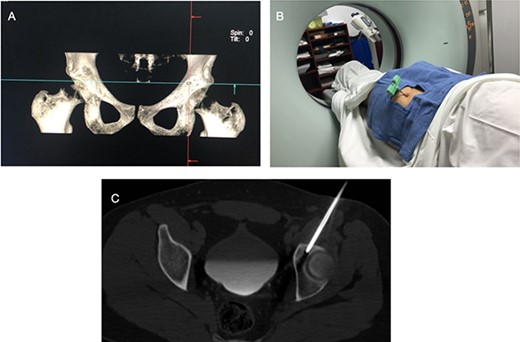

An 18-year-old male with 18 months of left hip pain was referred to an orthopedic surgeon for evaluation. Pain occurred with all hip movements, predominantly at night. Physical examination of the hip showed pain with deep palpation on the groin and positive test for flexion adduction and internal rotation and Patrick test. X-rays were obtained and femoroacetabular impingement (FAI) with labral tear was suspected (Fig. 1). A magnetic resonance imaging (MRI) showed no hip labrum or chondral defect. Measurements for bone deformities of cam and pincer were normal. Physical therapy and nonsteroidal anti-inflammatory drugs were prescribed with some pain relief especially at night. After no improvement of symptoms he was evaluated by a hip surgeon. Intra-articular hip injection with steroids was given and pain disappeared but nocturnal pain recurred after 24 h. Due to the clinical setting and poor response to pain management, an OO was suspected and (CT) was ordered where a 6 mm sclerotic bone tumor with a nidus in the anterior rim of the left acetabulum was identified and corresponded with the pain localization (Fig. 2).

CT scan of the left hip showing a 6-mm extra-articular OO on the anterior rim of the acetabulum (yellow arrow).